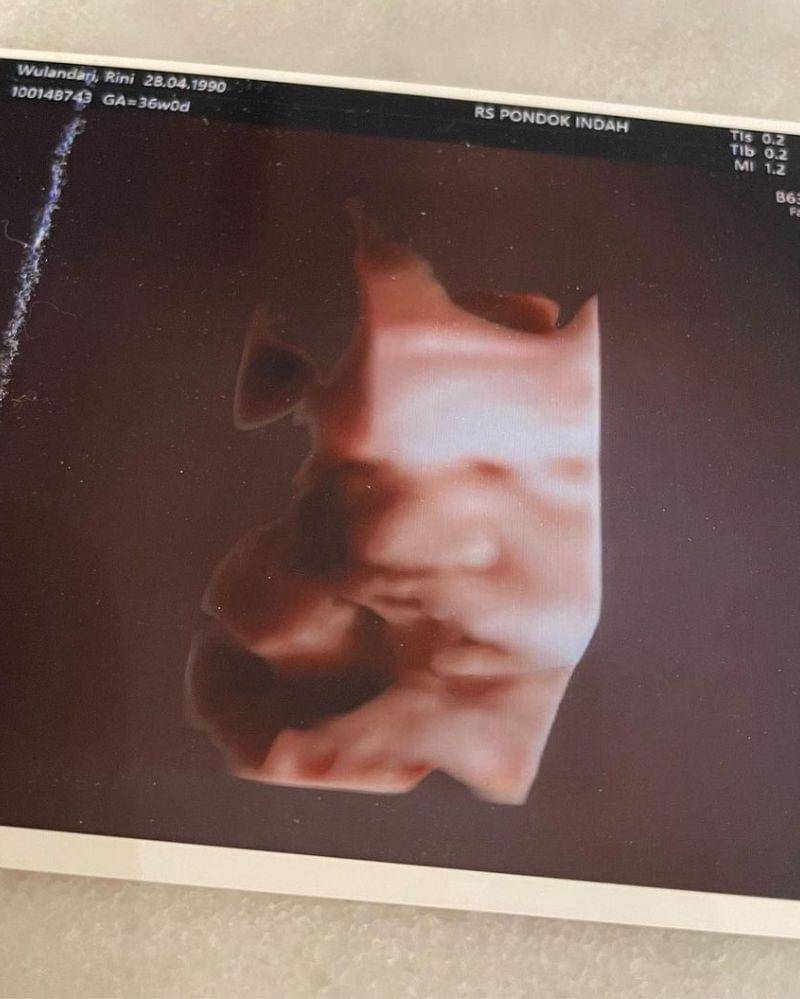

3. Lebih jelas, Rinni juga mengunggah foto ultrasound calon bayinya dari dekat

Secara terpisah, Rinni juga memamerkan foto ultrasound bayi laki-lakinya itu pada netizen. Ia bahkan memotretnya secara jelas dari jarak dekat.

Pada potret tersebut tampak wajah bayi laki-laki keduanya sudah terlihat begitu jelas. Netizen pun bisa melihat bagian mata, hidung, serta bibir si Bayi. Menurut Mama lebih mirip Mama Rinni atau Papa Jevin, nih?